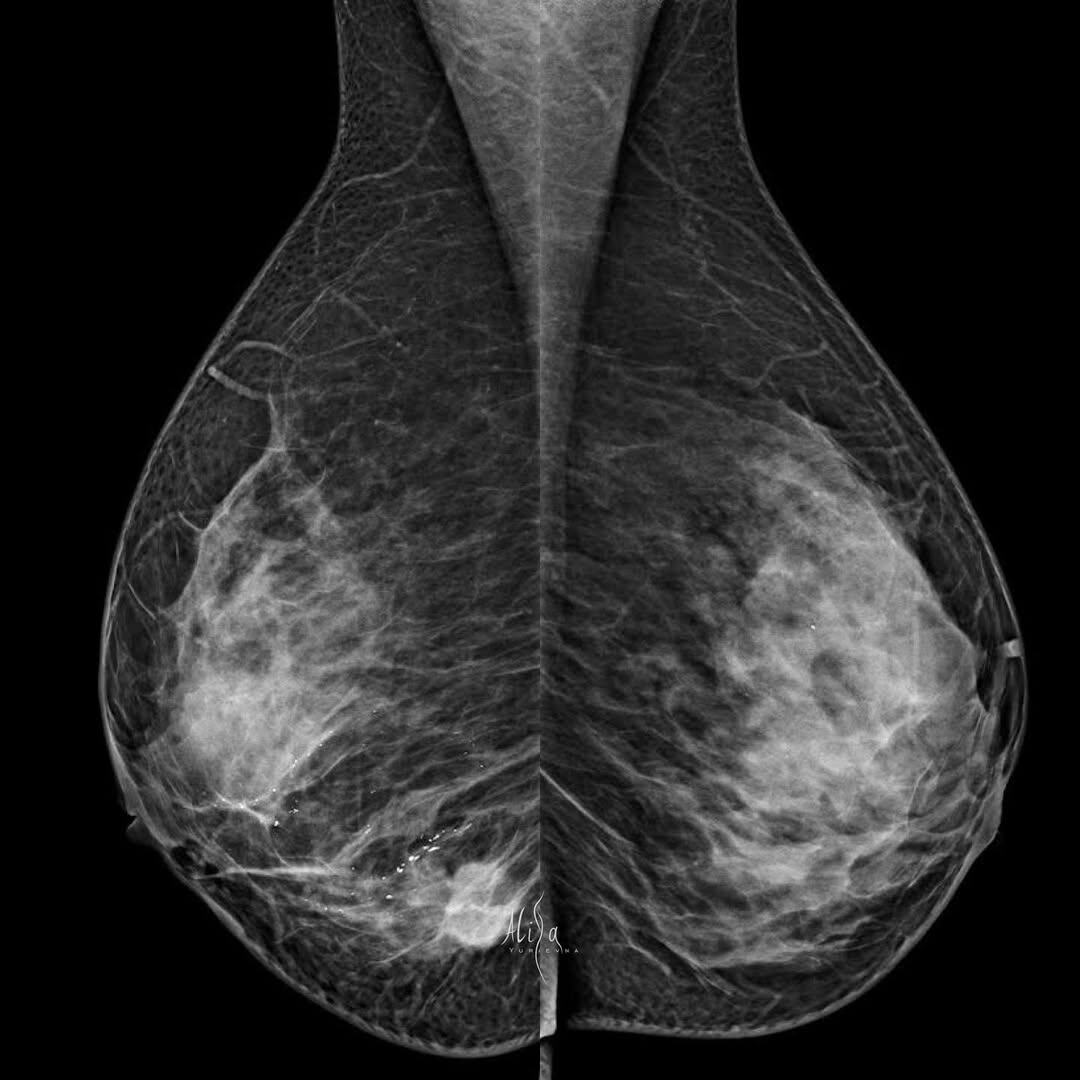

Женщина 1987гр 35 лет Или вроде ко мне вернулось оно…вдохновение. Частая история, когда привела маму на чек-ап и сама решила провериться. Странно, что раньше не замечала. Распространенный, конечно, процесс. Узлов несколько, кальцинаты на любой вкус. Ну и лу уже совсем бесструктурный. Люминальный В her2+++ Стандарт, томо, узи. Все как я люблю. #маммография #маммографияекб #привеламамуподумайосебе #маммографияспасаетжизни #диагностика #узи #томосинтез #мультимодальность #ракмолочнойжелезы

Женщина 1987гр 35 лет

Распространенный, конечно, процесс. Узлов несколько, кальцинаты на любой вкус.

Ну и лу уже совсем бесструктурный.

Люминальный В her2+++

Стандарт, томо, узи. Все как я люблю. #маммография #маммографияекб #привеламамуподумайосебе #маммографияспасаетжизни #диагностика #узи #томосинтез #мультимодальность #ракмолочнойжелезы